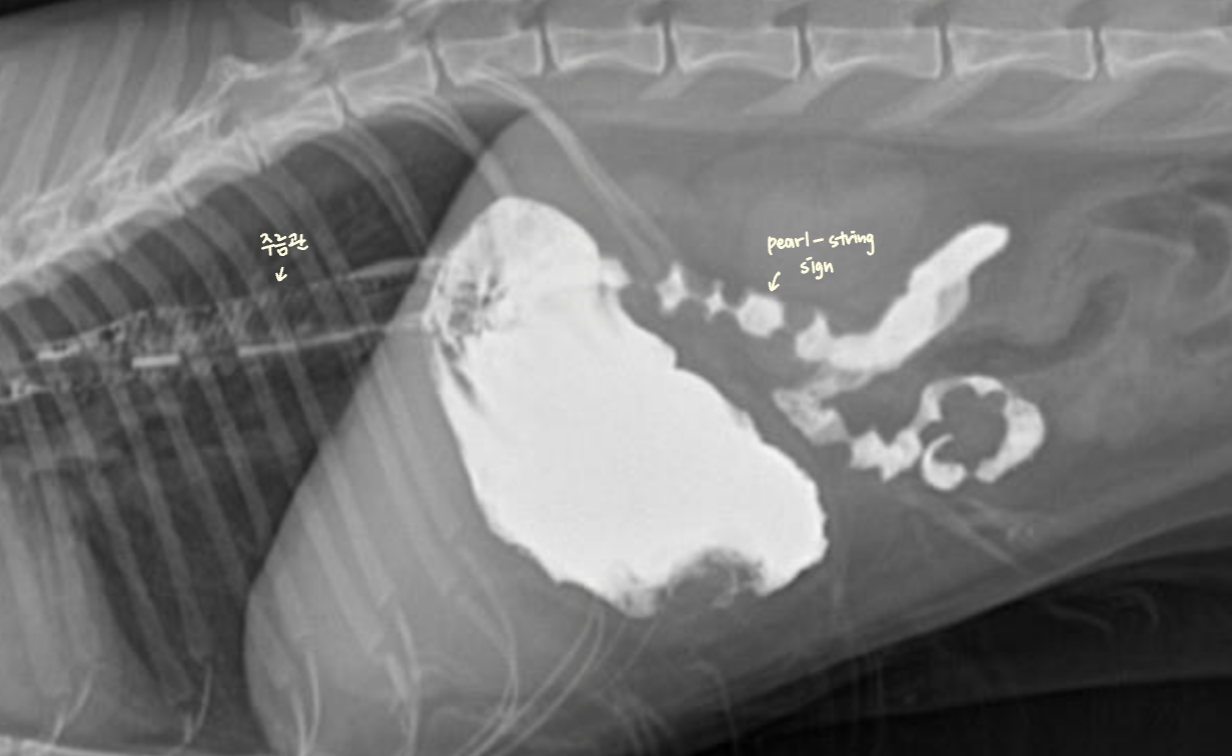

| ๊ณ ์์ด ์๋์ ํน์ง |

| - ์ฃผ๋ฆ๊ด ํํ์ ์๋ โ ์กฐ์์ ๊ฐ ์ผ์์ ์ผ๋ก ์ถ์ ๋์ด ์ค๋ฌด๋ฌ ๋ชจ์์ผ๋ก ๊ด์ฐฐ๋จ. |

| - ์์ฅ์ ๋ถ์ (pearl-string sign) : ๋ถ์ ์ด ๋ ์ ๋ณด์ฌ์ ์ง์ฃผ ๋ชฉ๊ฑธ์ด ๋ชจ์์ผ๋ก ๊ด์ฐฐ๋จ. |